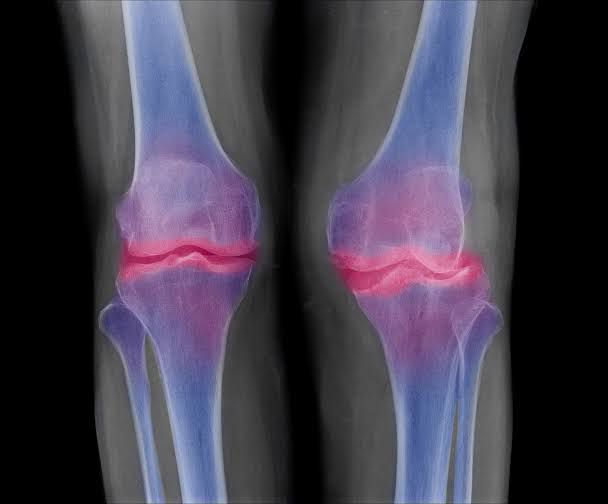

Marginal osteophytes are a common feature of osteoarthritis in the knee joint and other diarthrodial joints. These osseous outgrowths are formed in the periosteum at the junction between cartilage and bone, which is covered by synovium in diathrodial joints